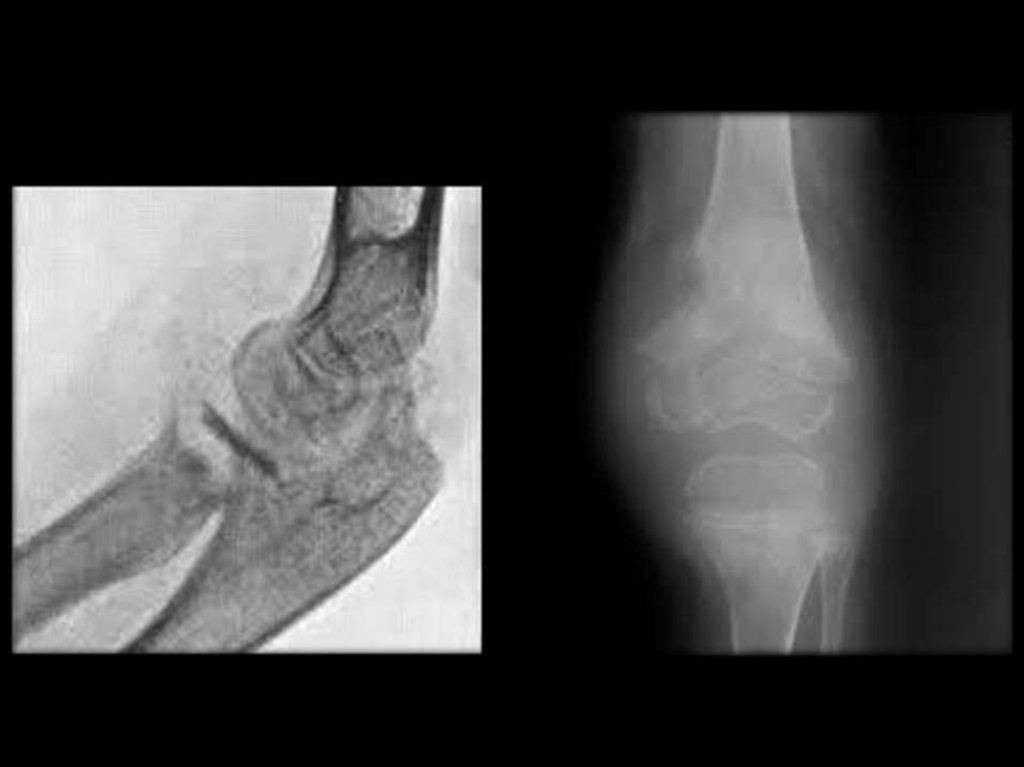

Острый гонорейный артрит левого коленного

сустава. Сгибательная контрактура.

Динамика рентгенологических изменений в

области суставов при хроническом сифилисе

Сифилитический артрит левого коленного

сустава, контрактура